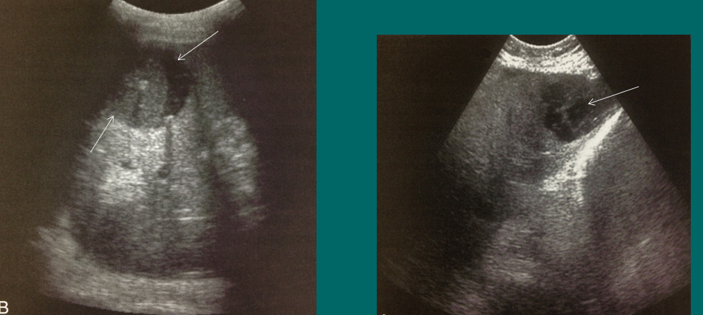

cavernous transformation of PV

schistosomiasis/bilharziasis

biliary complications

biloma (fluid collection)

ascites (fluid collection)